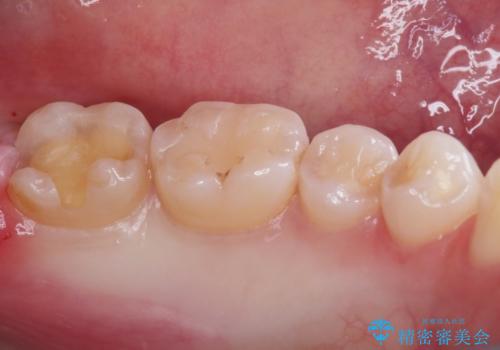

- 一番奥の歯の古い材料が劣化してしまい、欠けて黒くなっているのが気になるとの事でした。

詰め物のやりかえを提案したところ、セラミックインレーをご希望されたのでセラミックインレーにて治療をすることにしました。

古い材料と虫歯を除去して、型取りをしました。

適合も非常に良く、綺麗になりました。